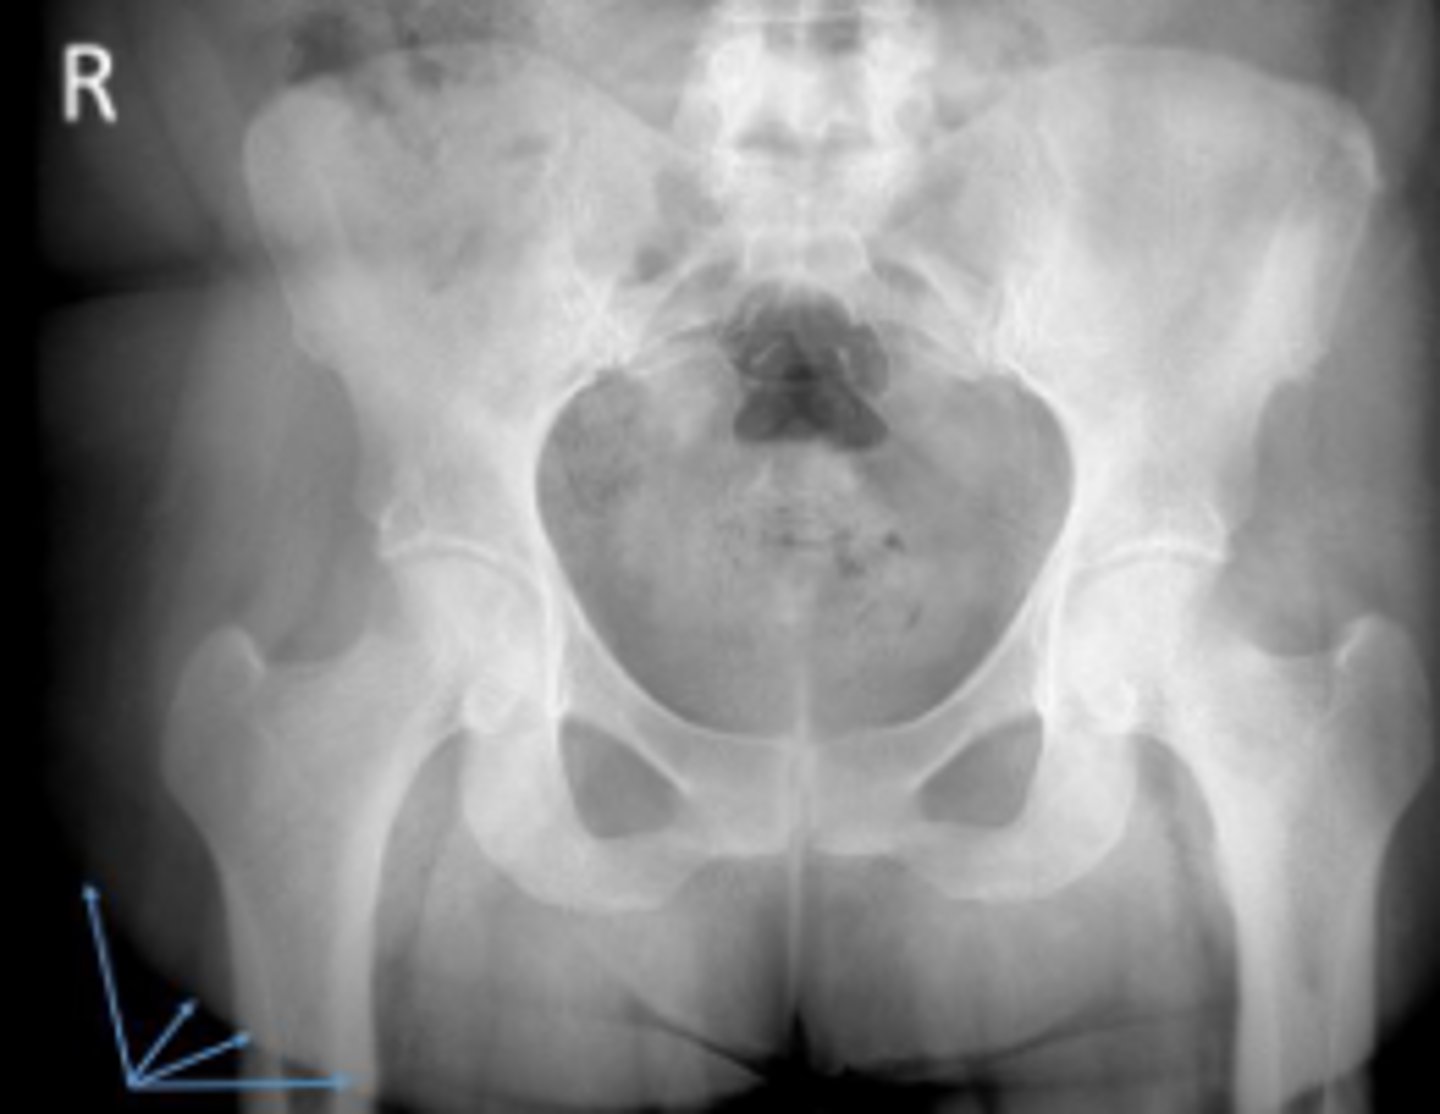

AP pelvis or bilateral hips

What is the name of the radiographic view?

PSIS

What are the arrows pointing to?

Phleboliths

Greater trochanter of the right femur

Greater trochanter of the left femur

Left and right posterior inferior iliac spine